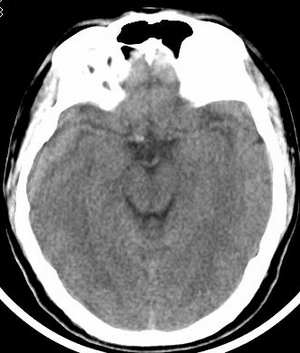

患者 男 45岁,头晕月余,无其它不适。

请大家看看大脑大静脉池里的条状影是什么?脑内静脉?